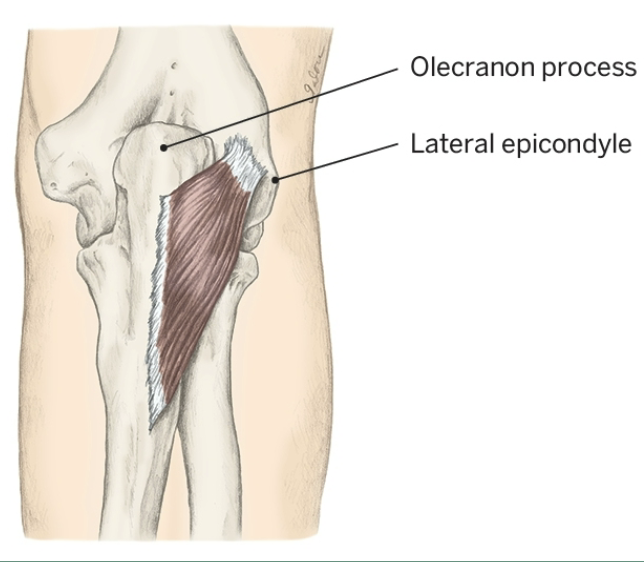

Action of Anconeus

Elbow Extension

Origin of Anconeus

Lateral epicondyle

Insertion of Anconeus

Olecronon process and posterior, proximal ulna

Nerve that the Anconeus innervates